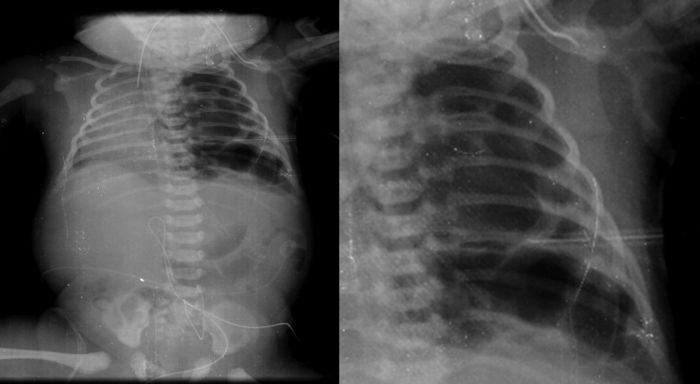

La primera radiografía (24 de enero del 2013) es la más demostrativa. Se observa el pulmón izquierdo lleno de imágenes radiolúcidas, bien circunscritas, de gran tamaño y que ocupan prácticamente todo el pulmón izquierdo. Las estructuras del mediastino así como el mismo pulmón izquierdo están desplazados hacia el lado derecho (Figura 1). El diafragma se observa aparentemente íntegro y hay poca distribución de gas intestinal. La cánula traqueal se encuentra en buena situación, pero lateralizada hacia la derecha. En una secuencia (3 de febrero) se observó una imagen radiolúcida a nivel basal de lado izquierdo en relación con un neumotórax que persistió, aunque de menores dimensiones. En el pulmón derecho se observaron cambios en la densidad en relación con un patrón de tipo reticular, lo cual no descartó la posibilidad de un proceso infeccioso. Por lo tanto, los diagnósticos radiológicos fueron una malformación congénita pulmonar de la vía aérea tipo I, un proceso neumónico pulmonar bilateral y neumotórax izquierdo. Las últimas placas fueron tomadas después de la resección del lóbulo superior del pulmón. Quedó un pulmón izquierdo muy pequeño, pero permitió que el pulmón derecho se reexpandiera. Quedó un neumotórax residual que es común en estos pacientes (Figura 2).

Figura 1 Imágenes de aspecto quístico que abarca todo el pulmón izquierdo y desplaza las estructuras del mediastino hacia la derecha.